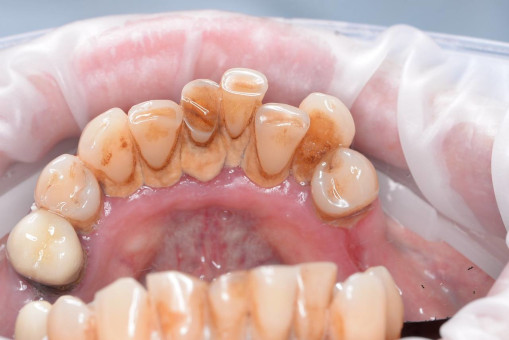

А прежде, чем вы посмотрите фотографии «до» и «после» лечения слизистой оболочки полости рта, проведенных в нашей клинике, хочу поблагодарить большое количество наших пациентов, которые поверили, прониклись нашей концепцией, и мы вместе, именно вместе победили болезни десны, гингивит и пародонтит!

До/после лечения